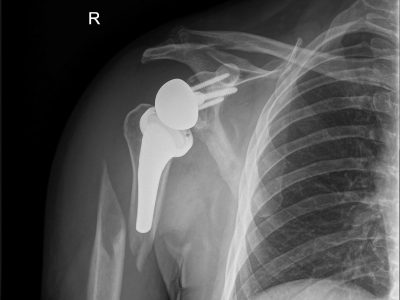

3. Κατάγματα /εξαρθρήματα ώμου και αγκώνα που χρήζουν αντιμετώπισης με Αρθροπλαστική.

Παρακάτω παρατίθενται ακτινογραφίες καταγμάτων του άνω άκρου που αντιμετωπίζονται με εσωτερική οστεοσύνθεση ή επανορθωτική χειρουργική με αρθροπλαστική.